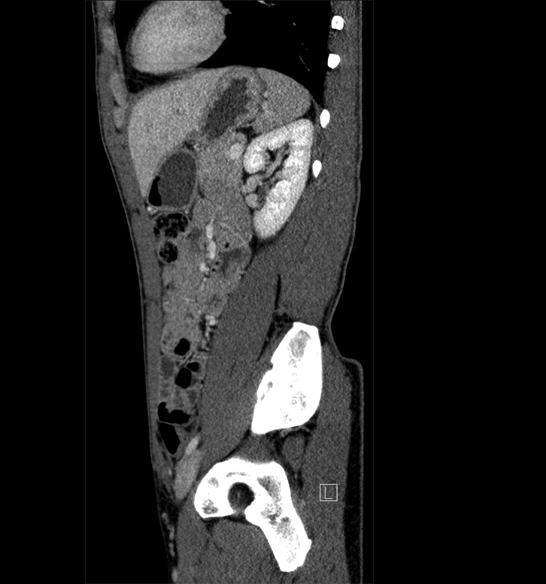

Body

Covers abdominal CT anatomy.